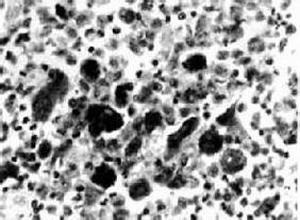

简介莱特雷尔-西韦病(Letterer-Siwe disease)是一种急性分化组织细胞增多病,发病年龄小,病变常侵犯多系统,眼和眼眶受累少见,预后很差。是郎格罕细胞组织细胞增生症的亚型